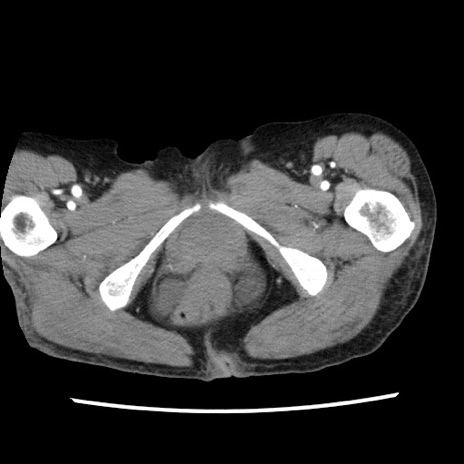

症例1(横断像)

【症例】80歳代女性

【主訴】腹痛

【現病歴】8時間前から腹痛あり来院。

【既往歴】糖尿病、脂質異常症、子宮体癌にて子宮全摘術

【身体所見】意識清明・会話良好だが腹痛で苦悶様、全腹部にわたって反跳痛と圧痛あり

【データ】WBC 13600、CRP 0.14、LDH 224、CK 90